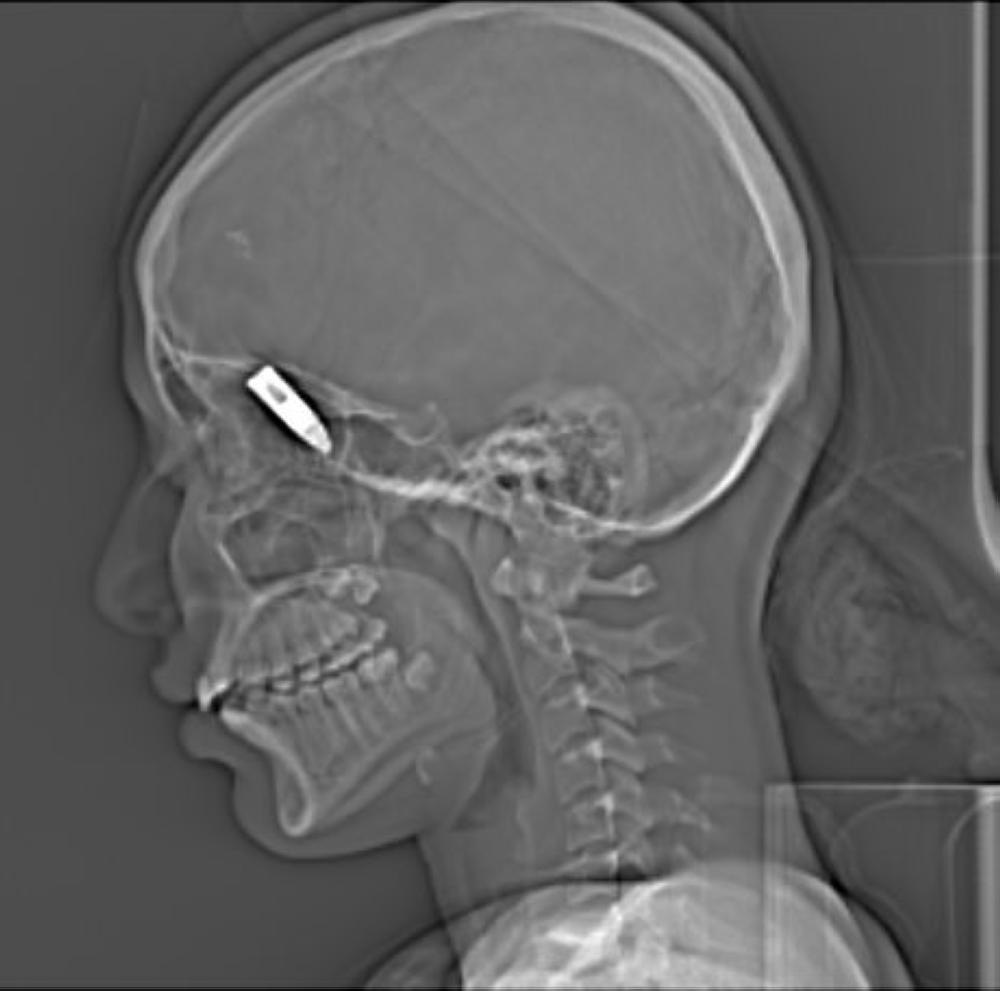

الرصاصة في جمجمة الفتاة. (عكاظ)

انتهت حفلة زفاف بوادي الدواسر بإصابة فتاة بطلق ناري اخترق رأسها، أثناء مرافقتها والديها في عرس أقاربهم بجنوب المعتلا، قبل أن تنقل على الفور إلى قسم جراحة الوجه والفكين بمدينة الملك فهد الطبيبة لاستخراج العيار الناري، الذي أظهرت صور الأشعة استقراره في جمجمة الفتاة. وأكد محافظ وادي الدواسر عبدالله المبارك أن الجهات الأمنية بالمحافظة تلاحق مطلقي النار في المناسبات، وتعمل جاهدة للقبض على المسيئين وعديمي المسؤولية بشكل عاجل. كما تتابع إحالتهم للنيابة العامة، لتطبق بحقهم الأنظمة التي تمنع ذلك؛ للقضاء على هذه الظاهرة التي تؤدي إلى العديد من الحوادث. كما اطمأن المبارك أمس الأول (الإثنين) على الحالة الصحية للفتاة عبر اتصال هاتفي بوالدها ضيف بن مسفر، عقب خضوعها للجراحة التي انتهت بنجاح، ما أدى إلى استقرار حالتها. بينما تقضي الفتاة بضعة أيام في المستشفى حتى تتماثل للشفاء.